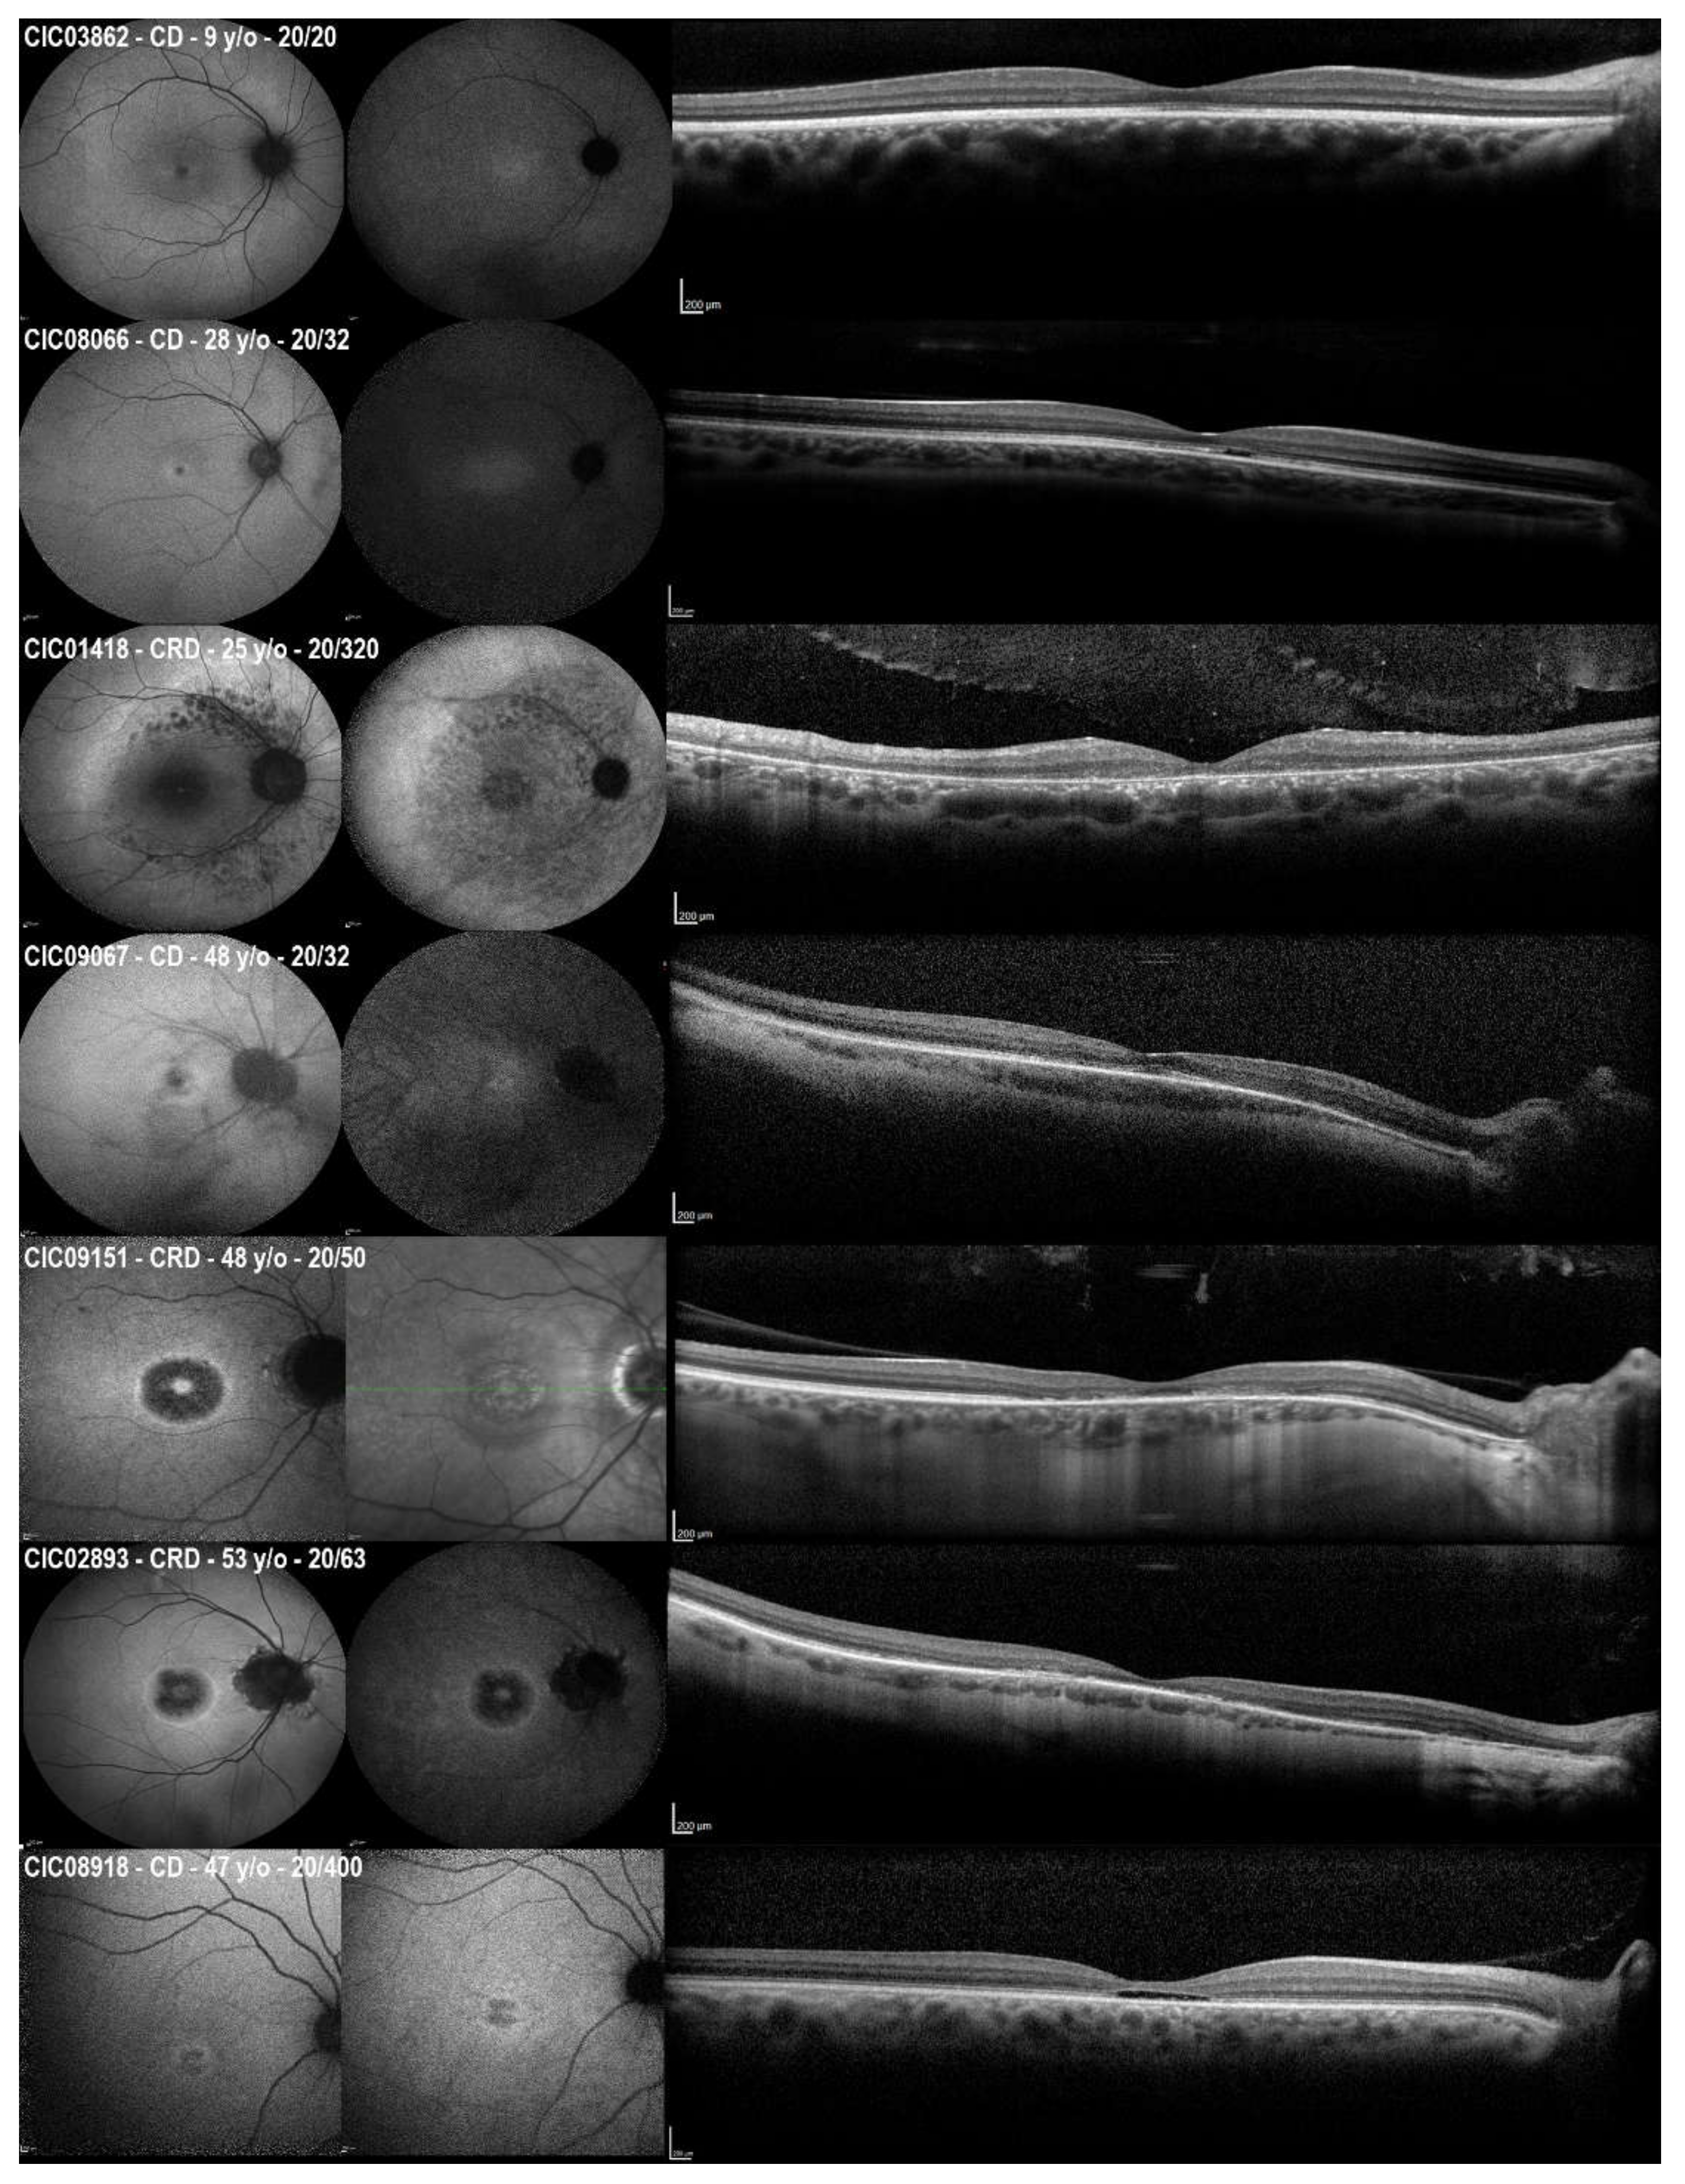

| ǂ CD/CRD, No/No | 15/21 |

| SW-FAF Phenotype type | n = 35 |

| Group 1 | 6 |

| Group 2 | 21 |

| Group 3 | 8 |

| Peripapillary sparing, No./Total No. (%) | 10/35 (28.57) |

| CRT, µm, mean ± SD | n = 35; 148.97 ± 27.17 |

| Unilateral or bilateral ERM, No./Total No. (%) | 2/35 (2.78) |

| Unilateral or bilateral iHRF, No./Total No. (%) | 15/35 (42.86) |